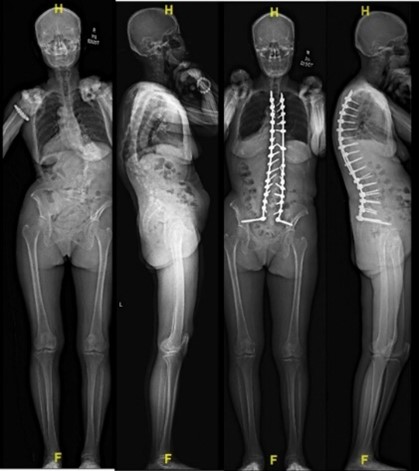

The Centre is also a recognised regional base for hands-on surgical training in thoracoscopic spinal surgery, spinal deformity surgery, cervical spine surgery, vertebroplasty as well as artificial disc replacement. The first of these instructional courses was conducted in 1990. In coordination with the National Scoliosis Screening Programme, the Spine Centre provides thoracoscopic, non-fusion (spinal tether) and conventional options for the surgical management of scoliosis. It was the first in the nation to perform artificial disc replacements of the spine in 2002. It has also sought to stay at the forefront of new and emerging techniques including endoscopic and minimally invasive spine surgery. In 2016, the Centre performed the first robot-assisted spine surgery in Singapore.

Amongst other achievements, the Spine group introduced interval halo-gravity traction for the treatment of very severe scoliosis curves, the use of O-arm navigated surgery employing paediatric radiation doses, the use of 3D printing in planning for complex spine curvature correction, the use of microdose EOS X-rays for scoliosis assessment, the intra operative use of spinal cord ultrasound post decompression to assess the adequacy of neural decompression and the introduction of endoscopic spine surgery.